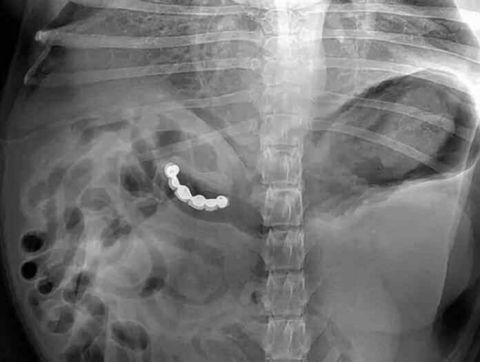

这里面装的*品毒**